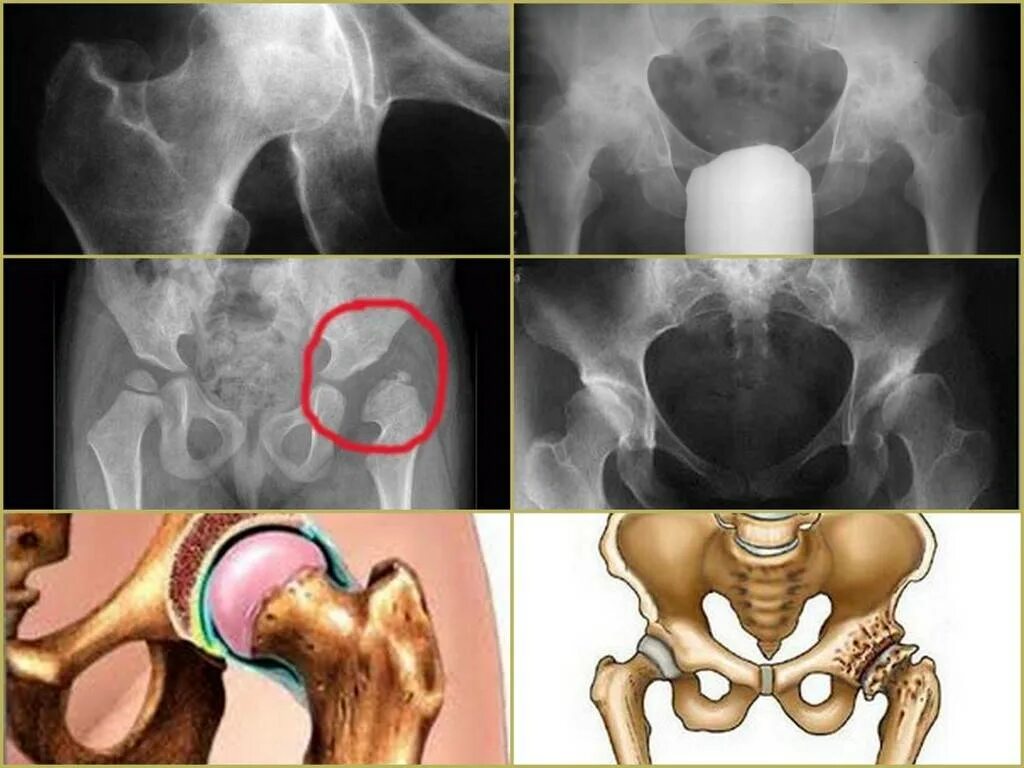

Тазобедренный сустав 3 степени лечение